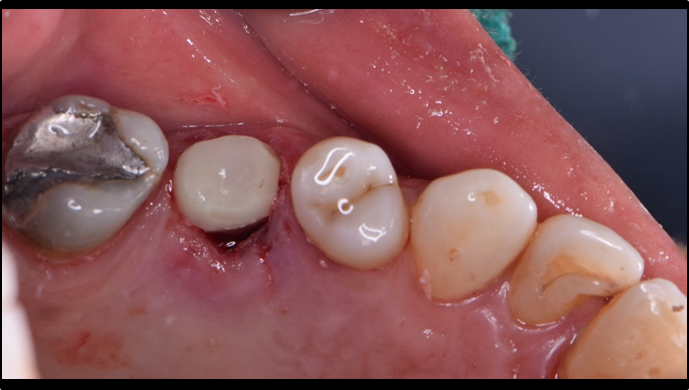

Clinical case: R2GATE GUIDE surgery with GBR

- Courtesy of Dr. Kwang Bum Park, Korea -

Dr. Kwang Bum Park, digital guided surgery, bone regeneration, maxillary posterior, #13, #14, guided surgery, GBR, AnyRidge, i-GEN, Mega-Oss, R2GATE, R2GATE Full surgical kit